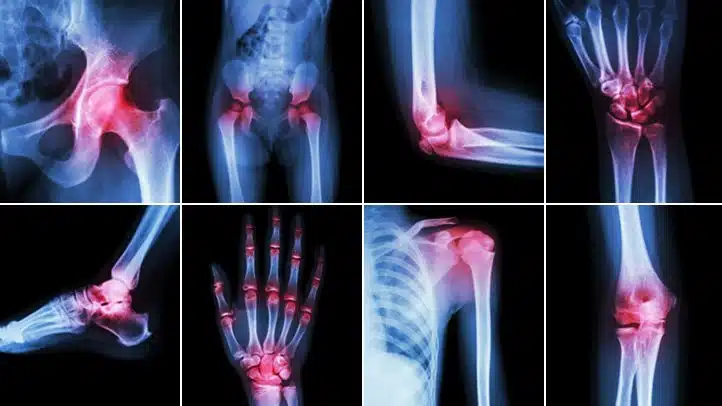

Osteoarthritis is caused by wear and tear of the joint over time or because of overuse. Rheumatoid arthritis, lupus, and scleroderma are caused by the body’s immune system attacking the body’s own tissues. Gout is caused by the buildup of crystals in the joints. Some forms of arthritis can be linked to genes.